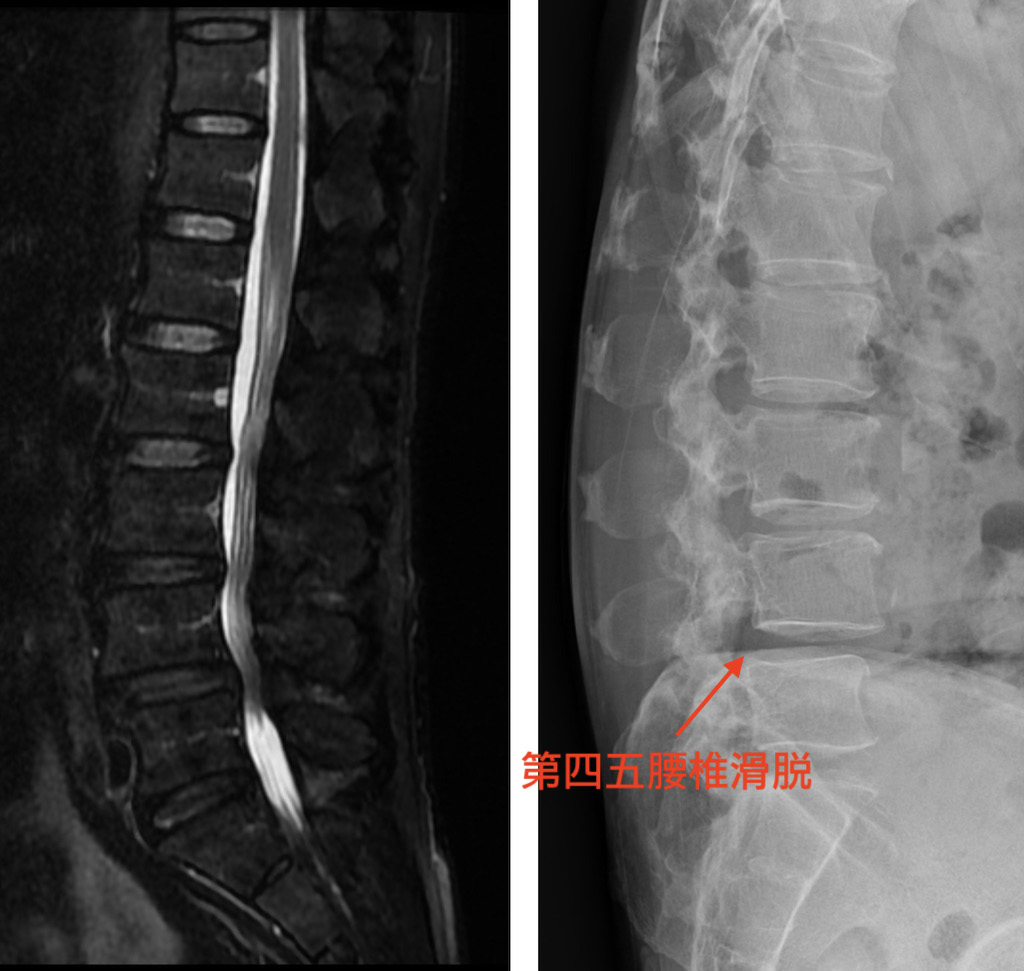

椎間管狹窄合併脊椎滑脫 用雙通道內視鏡脊椎微創手術做椎體融合術 陳奕霖醫師